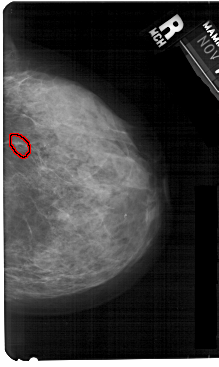

A_1367_1.RIGHT_MLO

RIGHT_MLO LINES 5491 PIXELS_PER_LINE 3466 BITS_PER_PIXEL 12 RESOLUTION 43.5 OVERLAY

FILE: A_1367_1.RIGHT_MLO.OVERLAY

TOTAL_ABNORMALITIES 1

ABNORMALITY 1

LESION_TYPE CALCIFICATION TYPE FINE_LINEAR_BRANCHING DISTRIBUTION CLUSTERED

ASSESSMENT 4

SUBTLETY 3

PATHOLOGY BENIGN

TOTAL_OUTLINES 1

BOUNDARY